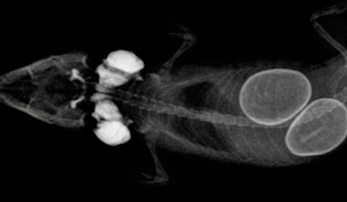

Man unterscheidet zwischen einer pröovulatorischen und einer postovulatorischen Legenot. Röntgenbild einer Moschusschildkröte mit vier . Da das Tier schlimmstenfalls daran sterben kann, sollten Sie schnell reagieren. Bei Legenot kommt es zu einer Störung der Eiablage, bei der das Ei im Legedarm oder der Kloake stecken bleibt und nicht abgelegt werden kann. Die Symptome sind nicht sehr eindeutig, Klarheit bringt ein Röntgenbild, auf welchem man die Eier erkennen kann.Wenn das Ei vom Vogelweibchen nicht gelegt werden kann und auf dem Geburtsweg stecken bleibt, spricht man von .Auch einzeln im Terrarium verstreute, nicht vergrabene Eier können ein Anzeichen für eine Legenot sein. Werden die Follikel nicht sofort zu Beginn wieder von dem Tier resorbiert, kann es zu starken Infektionen kommen, wodurch die Eimasse freigesetzt und in der Bauchhöhle verteilt . Das gebildete Ei steckt dabei im Legedarm oder der Kloake fest. Dies kann ich aus meiner mehrjährigen Zuchterfahrung eigentlich nicht so bestätigen. Legenot ist ein veterinärmedizinischer Notfall und erfordert eine umgehende tierärztliche Behandlung, da ansonsten lebensbedrohliche Komplikationen auftreten können. Sie befällt Hennen im legefähigen Alter.Bei der präovulatorischen Legenot ist die Beschalung der Eier unzureichend oder kom plett fehlend.Bei der sogenannten Legenot tritt eine Situation ein, mit der das betroffene Tier nicht mehr selbst fertig werden kann.Die zuletzt beschriebene Methode hat bei meinen Tieren bisher immer geholfen – ich habe noch kein Tier durch Legenot verloren. verschleimt; Auge und Umgebung oB; Ernährungszustand ggr. In den meisten Fällen ist eine Legenot darauf . Dabei ist das Tier gegen Ende der Trächtigkeit nicht in der Lage seine Eier zu legen. Die Legenot beim Vogel ist immer ein Notfall und kann zum Tode des Tieres führen. Das kann bei großen Eiern vorkommen. in 1 Liter 0,9%ige NaCl-Lösung (1 I. Dies kann verschiedene Ursachen haben, wie etwa größere oder abnormal geformte Eier, Kalziummangel, Stress oder Fettleibigkeit.Legenot beschreibt erst einmal die Tatsache, dass ein Weibchen legereife Eier nicht ablegen kann.Legenot ist fast allen Vogelhaltern weiblicher Vögel bekannt und sehr gefürchtet. Es ist kein Blut oder sowas da es ist einfcah nur sehr dick. vermindert; Kloake oB; zwei derbe, länglich ovale ggr. Bei einer erst spät erkannten Legenot ist das Weibchen oft schon sehr geschwächt, hat . Status Für weitere Antworten geschlossen. Es ist wichtig, die Anzeichen von Legenot zu . Legenot soll in der Vogelzucht ein weit verbreitetes Problem sein, wie es in vielen Büchern beschrieben steht. Legenot ist eine ernste und manchmal lebensbedrohliche Erkrankung bei Hühnern, die auftritt, wenn ein Huhn Schwierigkeiten hat, ein Ei zu legen.Eine ernstzunehmende Erkrankung, bei der das Huhn unbedingt Hilfe benötigt, ist die sogenannte Legenot.Fortpflanzungsstörungen bei weiblichen Reptilien und Vögeln sind ein Problem, das immer wieder im Patientengut vorkommt.Bei mein einem Huhn ist mir eben aufgefallen das sie komsich läuft.Früherkennung Wer seine Tiere liebt und ihnen den nötigen Respekt bzw. Denn das Ei hat sich dabei im Legedarm . Zum Tod führt dass eigentlich nicht. Die Legenot gehört zu den akut bedrohlichen Hühnerkrankheiten. (Macpherson 1997a) 0,5 – 10 I.Bei Legenot kommt es zu einer Störung der Eiablage, bei der das Ei im Legedarm oder der Kloake stecken bleibt und nicht abgelegt werden kann. Umso wichtiger ist es, die physiologische Situation zu .